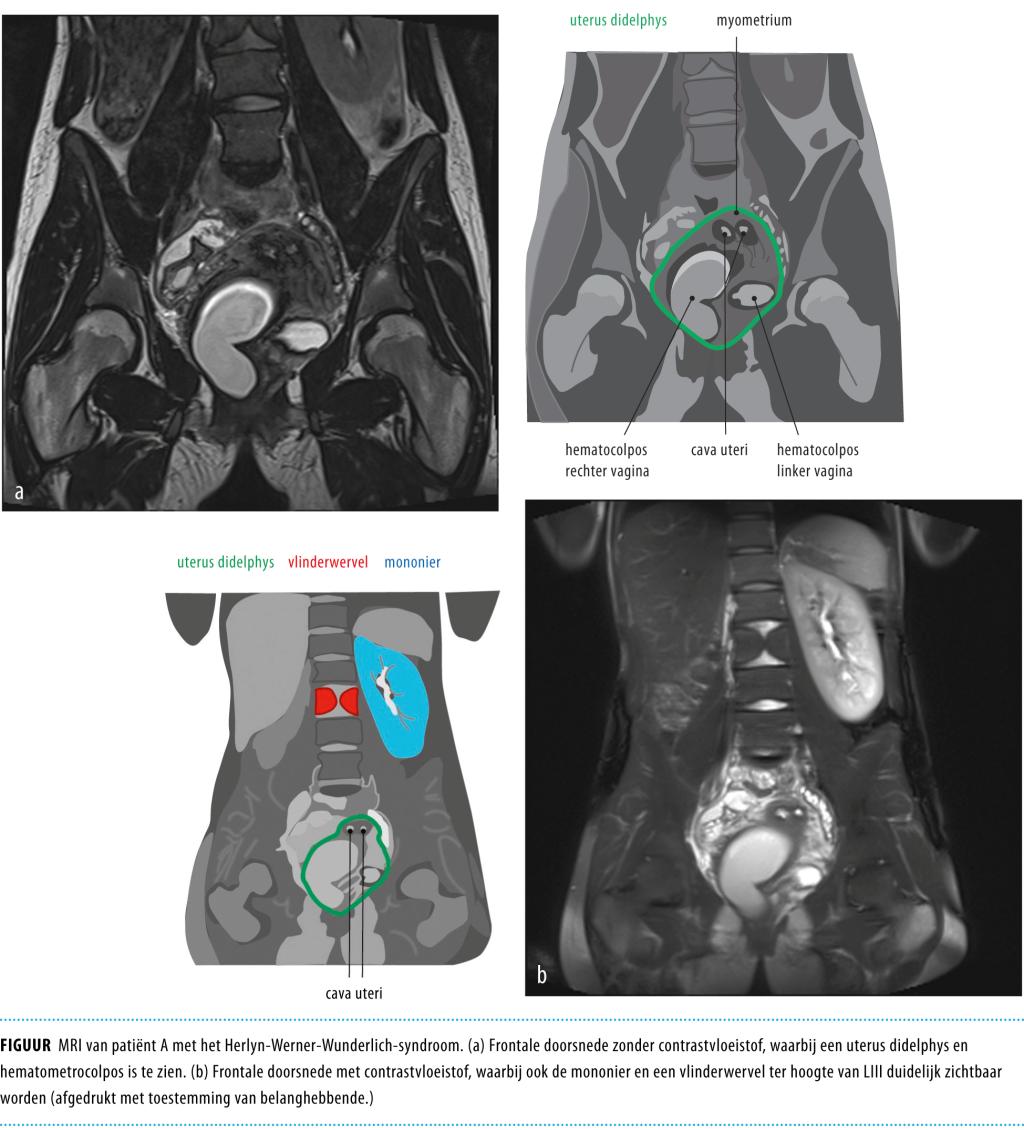

In de verklarende tekeningen bij de figuur waren anatomische structuren en afwijkingen niet correct aangegeven. Onderstaande figuur vervangt het figuur bij artikel A7886.

Op de Spoedeisende Hulp worden veel patiënten gezien met een acute buik. Een minder bekende oorzaak hiervan is het Herlyn-Werner-Wunderlich-syndroom. Dit kenmerkt zich door een uterus didelphys, een geobstrueerde hemivagina en een ipsilaterale nieragenesie of -dysplasie.

Wij zagen een 16-jarige vrouw met progressieve buikklachten en een nier- en anusafwijking in de voorgeschiedenis. Vanwege zowel druk- als loslaatpijn rechts onder in de buik en een verhoogde CRP-concentratie dachten we aan appendicitis acuta. Bij abdominale echografie zagen we een cysteuze structuur, vermoedelijk van ovariële of tubaire origine. Patiënte onderging een spoedlaparoscopie vanwege verdenking op een ovariumtorsie. Hierbij werd een uterus didelphys gezien met een afwijkend rechter systeem. Aanvullende diagnostiek met een MRI-scan toonde afwijkingen passend bij Herlyn-Werner-Wunderlich-syndroom.